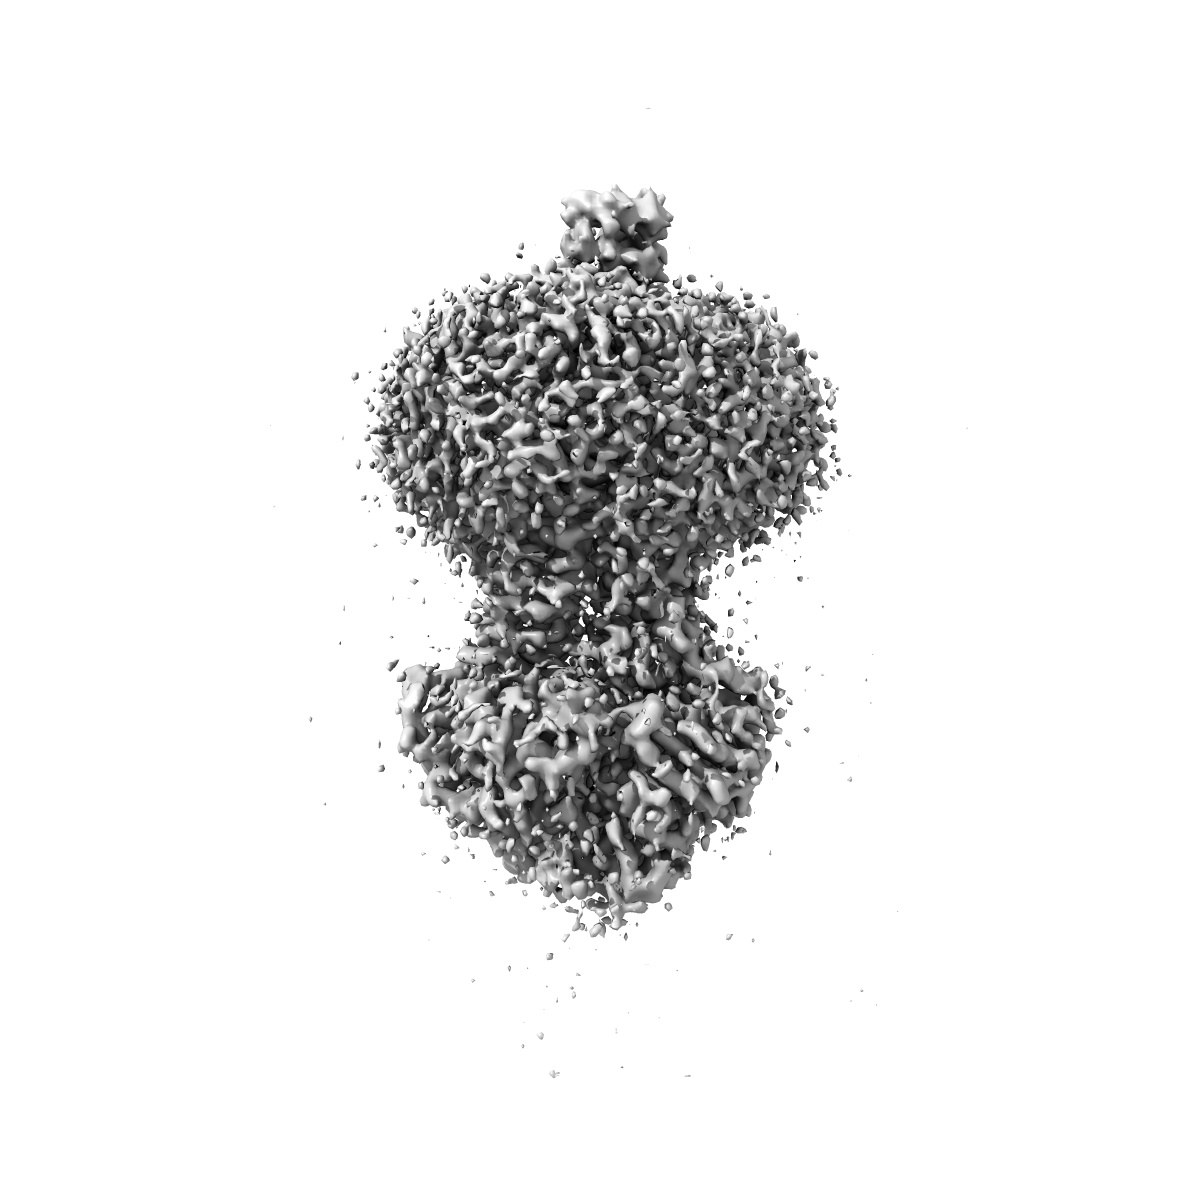

Cryo-EM structure of MsRv1273c/72c(E553Q) mutant from Mycobacterium smegmatis in the ATP-bound Occ state

Structure and mechanism of a mycobacterial isoniazid efflux pump MsRv1273c/72c with a degenerate nucleotide-binding site.

Yu J, Lan Y, Zhu C, Chen Z, Pan J, Shi Y, Yang L, Hu T, Gao Y , Zhao Y , Chen X, Yang X , Lu S, Guddat LW , Yang H , Rao Z , Li J

(2025) Nat Commun , 16 , 3969 - 3969